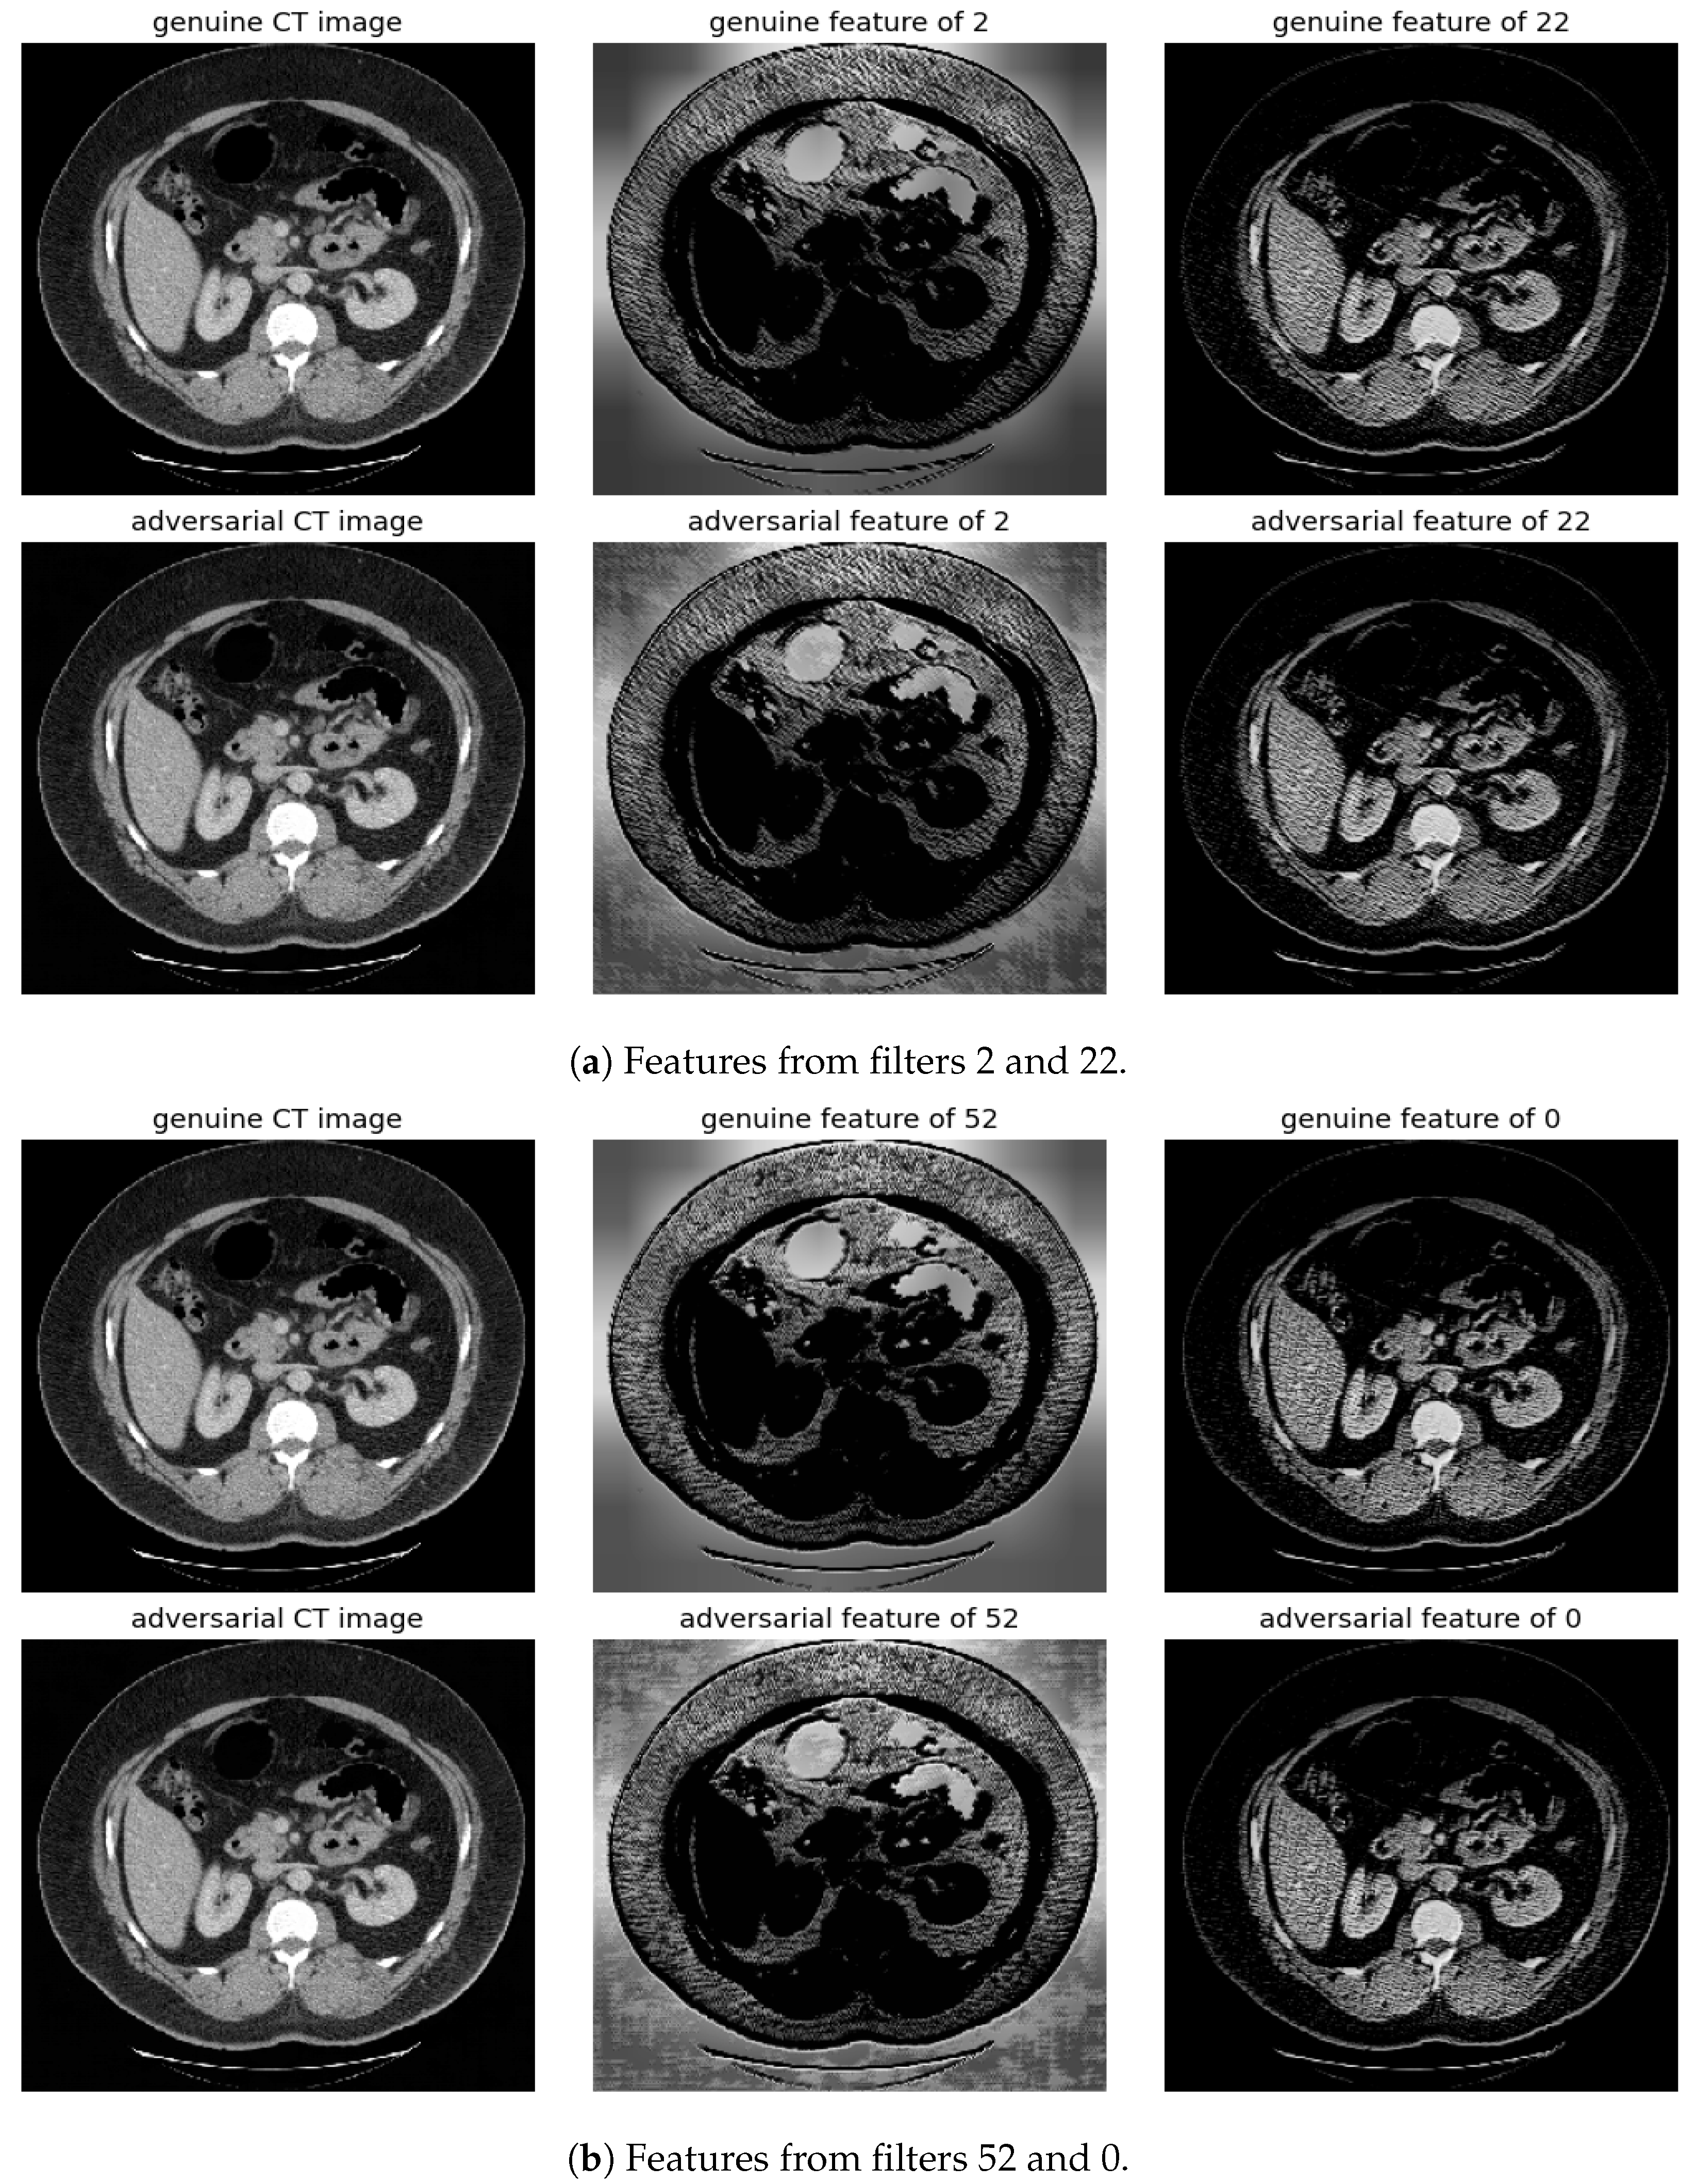

The significance of features associated with the most and least distinctive filters, specifically filter number 2 and filter number 22, is additionally examined. This analysis is conducted across FGSM, BIM, and SMIA for scenarios involving an epsilon of 0.01 and five iterations, excluding FGSM, as illustrated in Figure 7. The evaluation of feature importance is based on the mean decrease in impurity, a method used to assess how dependent variables impact prediction error in random forests [20]. The top 1% of features are presented according to their importance values. As indicated in the figure, the most distinctive feature predominantly concentrates on the background rather than the body, thus enabling easier distinction of adversarial samples from genuine ones. In contrast, the least distinctive feature primarily focuses on the structures surrounding the vertebrae, which may complicate the detection of attacks.

Randomly selected genuine CT samples, alongside their adversarial versions, are displayed in Figure 9, Figure 10 and Figure 11. The adversarial samples were generated using FGSM, BIM, and SMIA attack methods, each with an epsilon of 0.01. While BIM and SMIA used 5 iterations, FGSM did not. These samples represent the most challenging scenarios for human visual detection. Despite the modest epsilon value, as indicated in Table 3, the adversarial attacks have a subtle but pronounced effect. Such slight modifications can lead to major diagnostic inaccuracies potentially impacting patient care.

To address this, histogram equalization as feature post-processing is applied. The visual representations underscore that while genuine and adversarial samples might appear similar to the naked eye, post-processing brings forth distinct feature differences when employing the most sensitive filters from 2 and 52. Perturbations, especially noticeable in the background of the adversarial samples, are frequently highlighted by these filters. Conversely, features processed with filters from 22 and 0, deemed less sensitive in prior analyses, fail to offer a stark visual contrast.

Figure 10. Visualization under BIM Attack: Comparisons of features from the first layer between genuine and adversarial samples for the most sensitive (filters 2 and 52) and least sensitive (filters 22 and 0) filters.

Figure 11. Visualization under SMIA Attack: Comparison of features from the first layer between genuine and adversarial samples for the most sensitive (filters 2 and 52) and least sensitive (filter 22 and 0) filters.